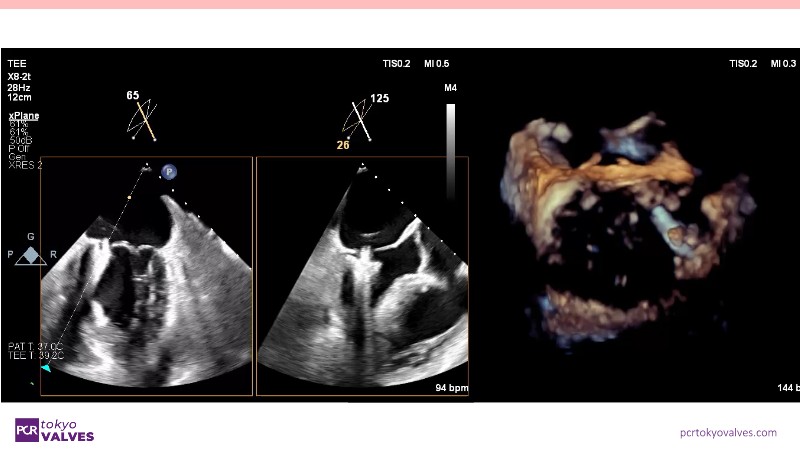

Explore the latest advancements in TEER therapy with this PCR Tokyo Valves 2025 session dedicated to MitraClip. Through expert-led case discussions, gain a deeper understanding of complex scenarios, including restricted posterior leaflet in functional mitral regurgitation, commissure lesion (A3P3), and MitraClip combined with Amulet.